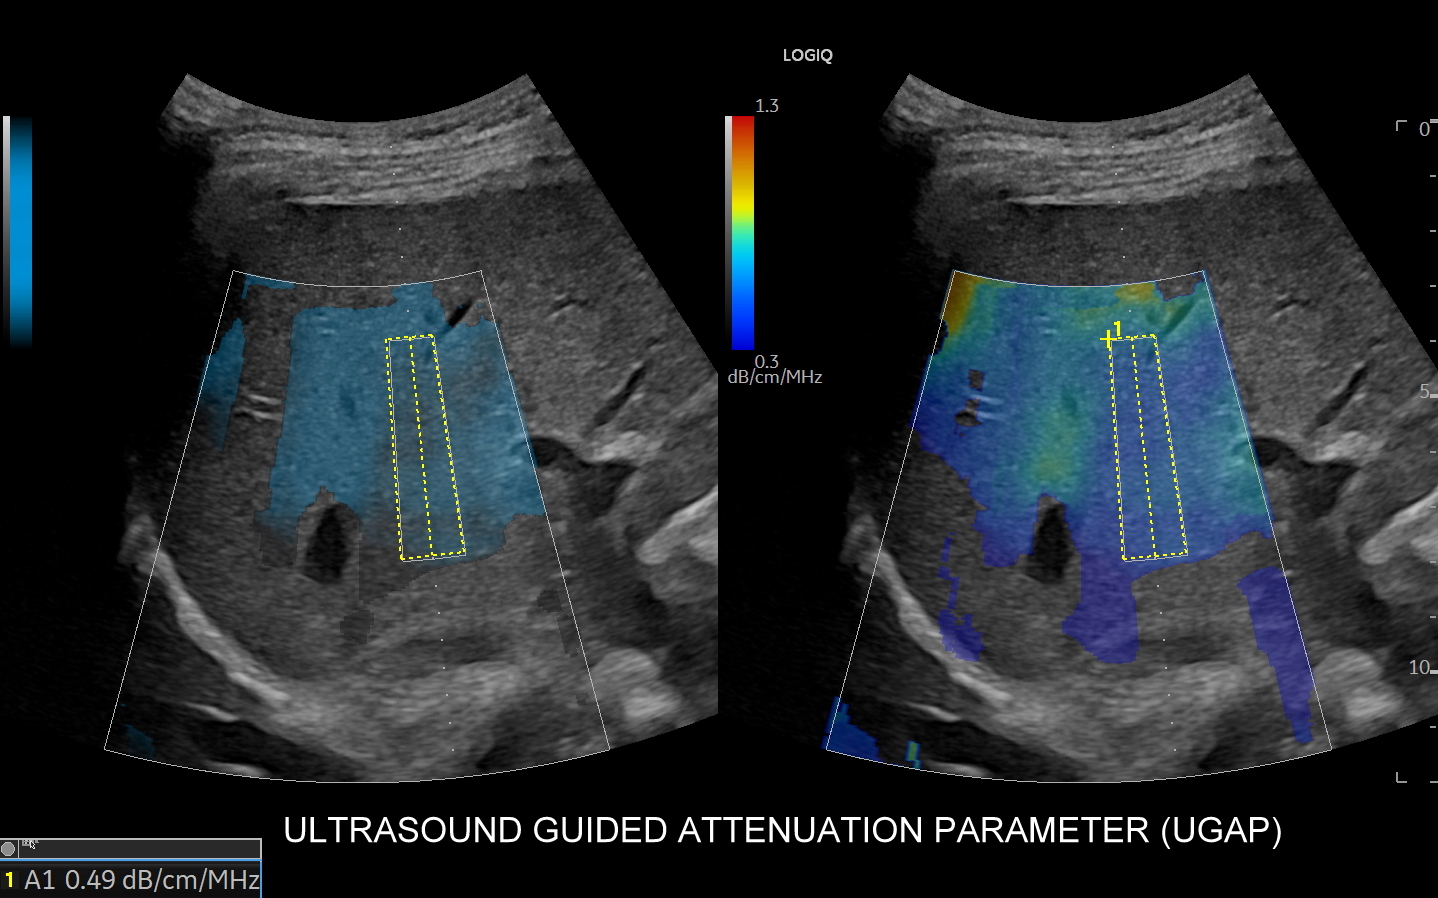

W ramach kompleksowej oceny wątroby elastografię 2D-SWE warto jednoczasowo połączyć z przeprowadzeniem badania USG przepływów wątrobowych oraz oceną stłuszczenia wątroby QUS w ramach kompleksowego badania MPUS brzucha. Podczas rejestracji zapytaj się o Multiparametryczne badanie USG / MPUS jamy brzusznej >